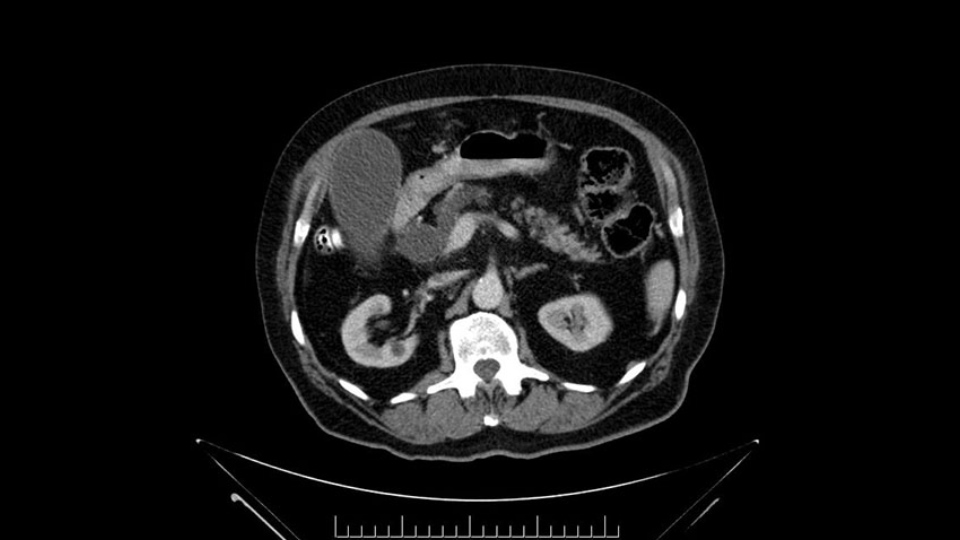

The next item that I would look at: the issue would be the vessels and usually start at the portal vein, watch the portal vein, follow it down, down-down-down to the neck of the pancreas - which is here - and there’s no impingement by tumor, which is great. The SMV and the splenic vein, which is here. The splenic vein junction is normal, which is great.

Then look at the first jejunal branch - which is this thing here - this little branch which goes under the SMA. It’s something that we’ve just started appreciating over the past few years and the reason for that is: there’s two or three small branches that come out of the uncinate into the the first jejunal and it’s a fairly inevitable part of the operation where there’s some bleeding. As long as you’re cognizant of what’s happening, it’s no reason to panic and that kind of bleeding will eventually stop or can be stopped but it’s not easy because these little vessels are fragile from the uncinate to the first jejunal. So I do focus on that and it’s pretty consistent I’d say 9 times out of 10, people have that first jejunal.

The other thing I look at is the gastroepeiploic arcade- which is this thing here- which is where the gastroepeiploic vein joins the portal vein. I call it the gateway to the neck of the pancreas because you pretty much have to divide it to get to the neck. The middle colic vein usually drains either into it or nearby. I think we’re seeing it here. Again,that can be divided and I usually divide those two and it helps me get under the neck. Again, there’s no issues here with the tumor so it’s nice from that perspective. If I was concerned about the vein, which I’m not here, I would go to the coronal view. It’s a nice way to look at the vein on just a couple of cuts and you can see a beautiful view of it here. There’s the portal vein, there’s the head of the pancreas. There’s the tumor. It’s a little closer here than it looks on the other one. I doubt it’s involved. If it’s touching, it may not be invading it but even if it was, it's a short segment. Anyways, there’s the SMV there’s the splenic vein, and everything looks good. You can see the stent. I ignore the stent. It’s the most dramatic looking thing in the picture but it’s actually the least important.